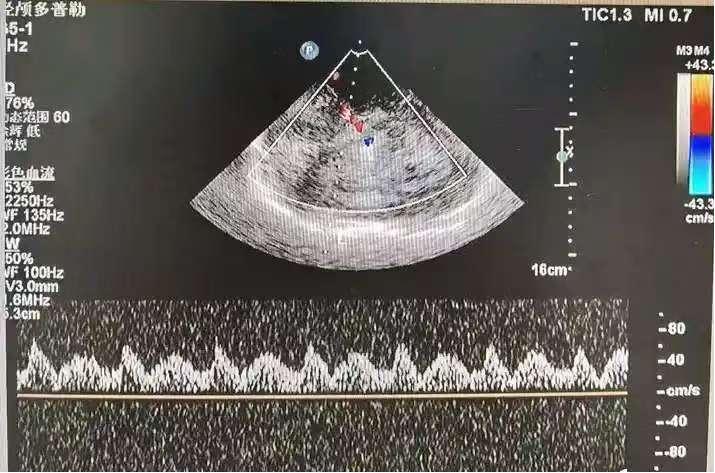

多普勒超声(TCD)

通过检测血流速度的变化,多普勒超声是一种微创检查方法,可以评估血管的健康状况。

多普勒超声检查时,医生会用超声探头移动患者颈部血管,捕捉血管内血流的声波信号。经过处理,这些声波信号可以显示出血管的狭窄、扩张、血流方向和血流速度。一旦发现血流速度异常,可能会提醒血管狭窄或堵塞,这对脑血管疾病的诊断具有重要意义。